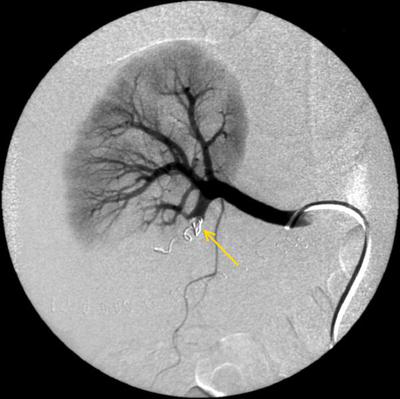

Хирургические процессы при эмболизации гемангиомы на фото

Раздел: Снимки-откровения